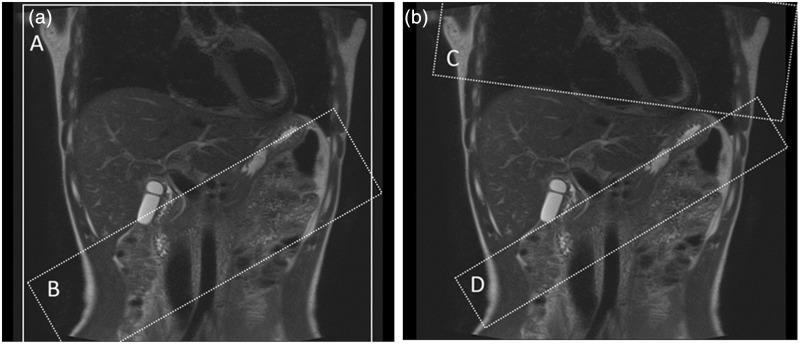

Twenty-five healthy volunteers were examined using respiratory-triggered three-dimensional balanced steady-state free-precession (bSSFP) with Time-SLIP. For portography, we used one tagging pulse (selective inversion recovery) and one non-selective inversion recovery pulse; for venography, two tagging pulses were used. The relative signal-to-noise ratio (SNR) and contrast-to-noise ratio (CNR) were quantified, and the quality of visualization was evaluated.

材料与方法

25名健康志愿者采用呼吸触发三维平衡稳态自由进动(bSSFP)结合Time-SLIP进行检查。对于门静脉造影,我们使用一个标记脉冲(选择性反转恢复)和一个非选择性反转恢复脉冲;对于静脉造影,使用两个标记脉冲。对相对信噪比(SNR)和对比噪声比(CNR)进行量化,并评估可视化质量。